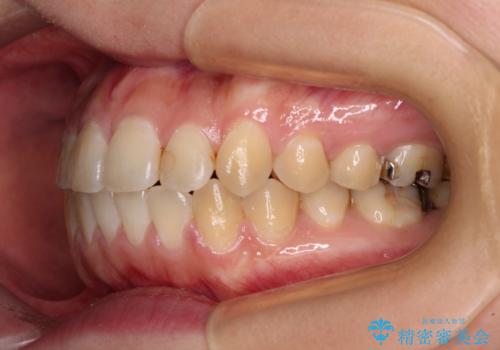

- 前歯のデコボコを気にして来院された患者様です。

前歯のデコボコはもちろん気になるところですが、舌の突出癖により上下前歯が非接触となっている状態でした。

上下前歯が非接触である開咬は、インビザラインによる治療がお勧めではありますが、しっかりと使う自信がないとのことで、ワイヤー装置にて治療を行うこととしました。

デコボコはあっという間に改善されましたが、開咬の改善に時間がかかりました。

舌の突出癖改善のトレーニングをしっかりと行っていただき、上下前歯が接触する咬み合わせを達成することができました。